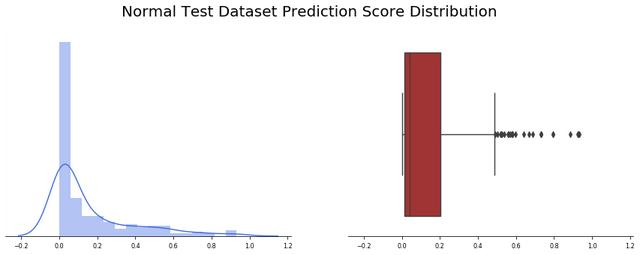

我们观察了234张诊断为正常的“未公开”图片(还有390张不是由Covid-19引起的肺炎)。应用批处理函数,我们观察到24幅图像出现假阳性(约10%)。让我们看看模型输出值是如何分布的,记住函数返回的值计算如下:

pred = new_model.predict(image)pred_pos = round(pred[0][0] * 100)

我们观察到,预测精度的平均值为0.15,并且非常集中于接近于零的值(中值仅为0.043),有趣的是,大多数误报率接近0.5,少数异常值高于0.6。

除了改进模型外,研究产生假阳性的图像也是很有意义的。